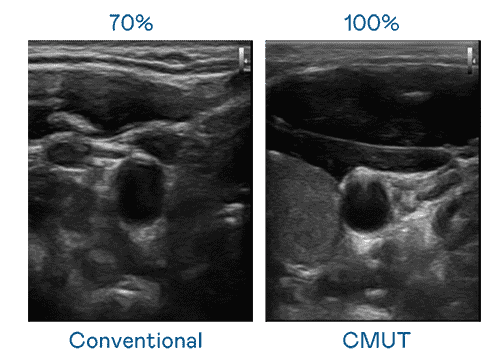

CMUT 技术是一种用电容式微机电元件来产生超音波讯号的技术。。。与传统 PZT 压电式技术相比,,,CMUT 频宽增加 30%,,,,更宽频的超音波讯号让影像解析度大幅提升,,是实现高影像品质医疗超音波扫描、、、促进精准医疗发展的关键技术。。。。

超音波影像的解析度高低,,首先取决于探头能发出的讯号频宽。。。。杏悦2 CMUT 可提供高清晰的超音波讯号,,,提供高频宽、、高灵敏度、、、、影像纹理细节更高的超音波影像,,协助医护人员缩短影像判读时间及利用精准的医疗影像进行诊断。。